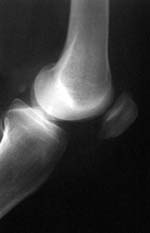

Las radiaciones de Rayos-X abarcan desde los 3,0 x 1016 (30 PHz), hasta los 3,0 x 1019 Hz (30

EHz) de frecuencia dentro del espectro electromagnético. Las radiaciones de esos rayos son

invisibles para el ojo humano, pero pueden atravesar diferentes tipos objetos, incluyendo el cuerpo humano.

Sin embargo, las planchas de plomo no son atravesadas por los Rayos-X, por lo

que se emplea normalmente ese metal para proteger al hombre cuando trabaja con aparatos que

emiten este tipo de radiaciones.

Los Rayos-X, descubiertos a finales del siglo 18 por el físico alemán Wilhelm Röntgen, se emplean

fundamentalmente para obtener radiografías de apoyo al diagnóstico médico, así como en investigaciones metalúrgicas, científicas y

en el análisis de obras de arte.

Radiografía obtenida por Rayos-X.